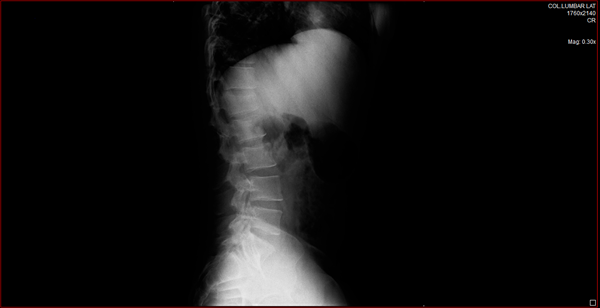

¿Qué es lo que tengo fracturado según la imagen?

¿Es una fractura de vértebra? Las vértebras no es lo que he subrayado de color rojo, el resto que parece fracturado qué es realmente porque no lo tengo claro. Me podéis orientar un poco más al respecto. Muchas gracias